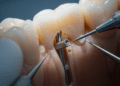

O diagnóstico é realizado por meio da anamnese, exame clínico e testes sensoriais. O dentista deverá analisar os sintomas descritos pelo paciente e avaliar a vitalidade da polpa com métodos que incluem:

- Inspeção clínica: Análise de restaurações, presença de fissuras, fraturas ou desgaste dentário.

Os sinais indicativos de pulpite reversível são sensibilidade rápida e passageira ao estímulo, ausência de dor espontânea e exames complementares que confirmem a integridade pulpar.